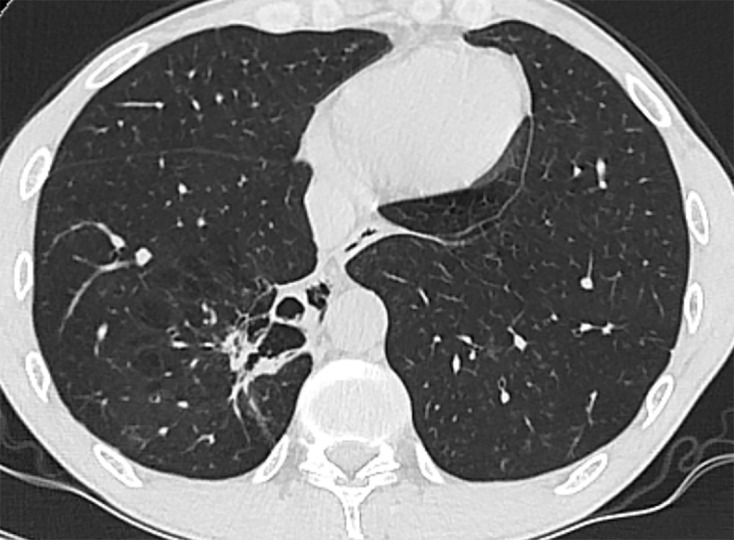

Background: Pulmonary sequestration is a congenital malformation in which nonfunctional lung tissue develops without connection to the bronchial system. The main complication is the occurrence of recurrent pneumonia.

Case presentation: We describe the case of a patient who was incidentally diagnosed with PS as part of the diagnostic algorithm for community-acquired pneumonia. Due to the relatively late diagnosis, the recurrent bronchopulmonary was conducive to the development of COPD and pulmonary emphysema. For prognostic reasons, surgical resection was performed by posterolateral thoracotomy.